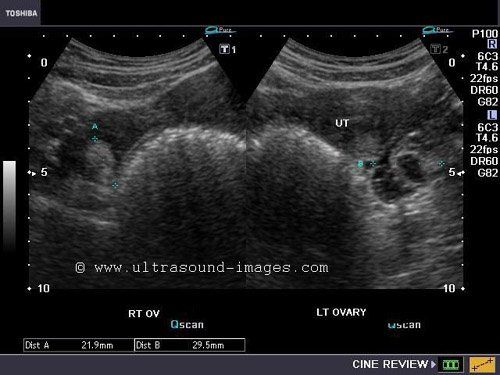

Vaginal ultrasound

Vaginal ultrasound 112 photos